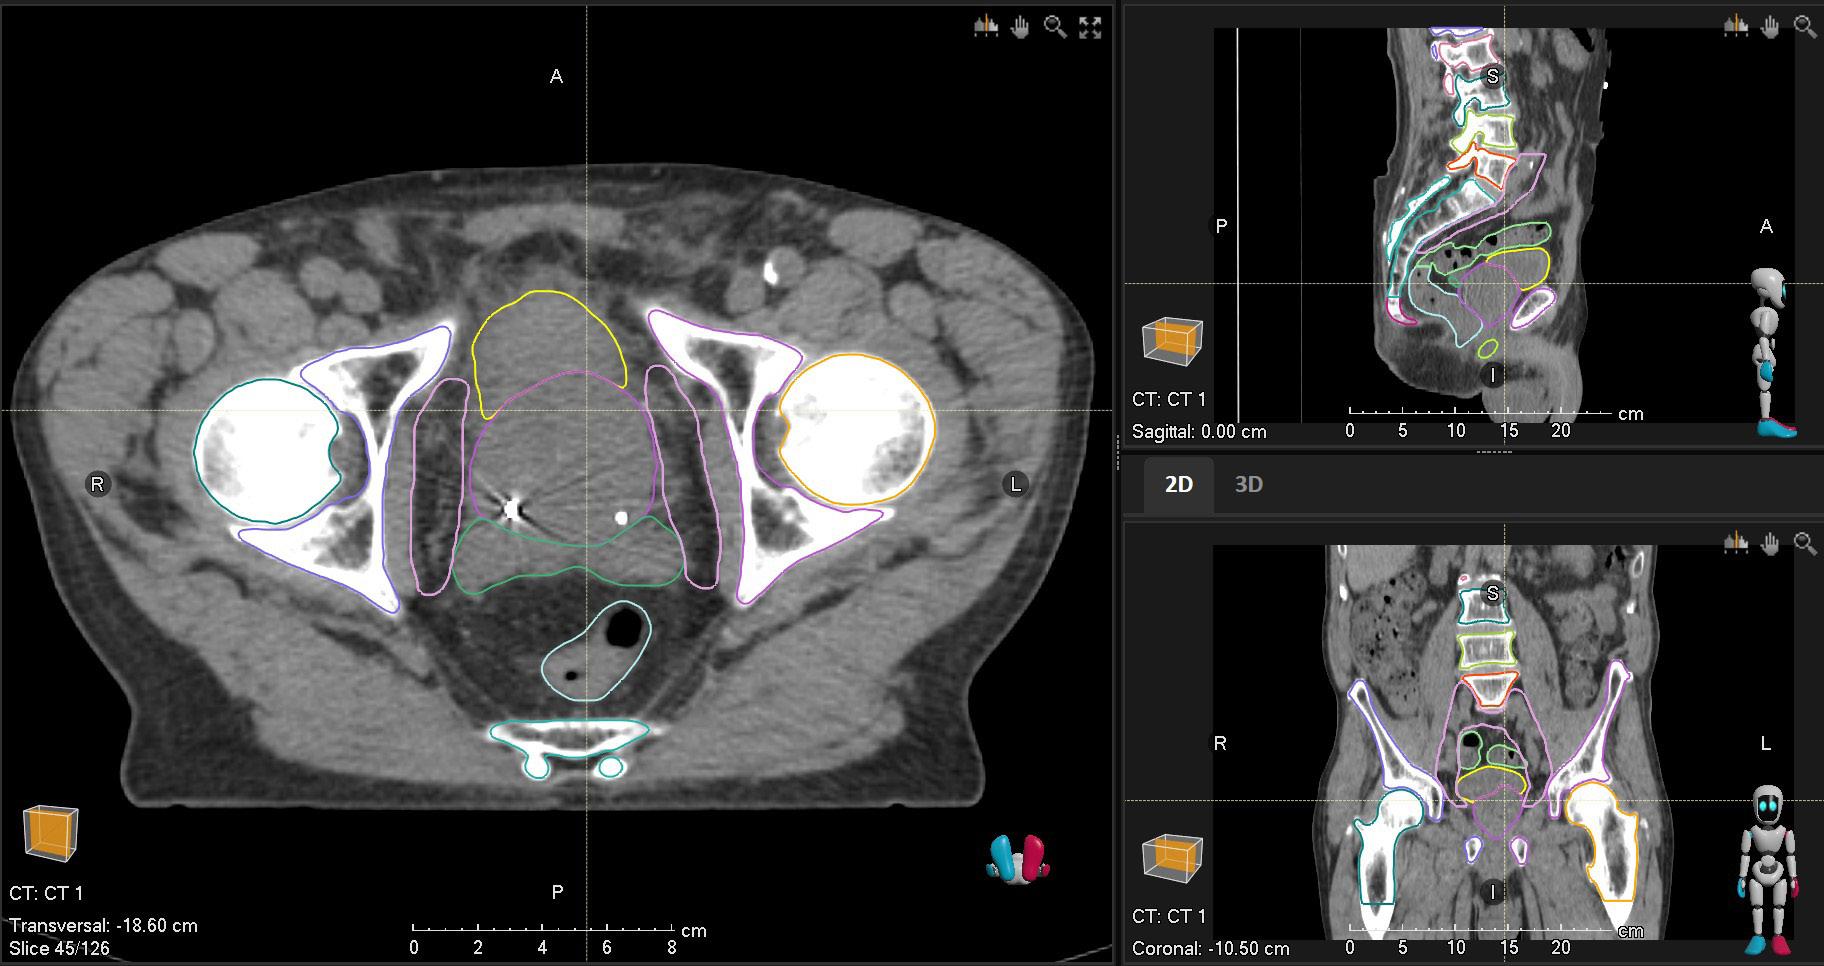

MALE PELVIC CT

STRUCTURES

Anorectum Musc_Iliopsoas_L NEW *

Bladder Musc_Iliopsoas_R NEW *

Bone_Pelvic_L NEW * PenileBulb NEW

Bone_Pelvic_R NEW * Prostate

Coccyx NEW * Prostate_minus_VenousPlexus

Colon_Sigmoid NEW Sacrum NEW *

Femur_Head_L * SeminalVes

Femur_Head_R * Spc_Bowel

LN_Pelvics NEW

*Also works for female pelvic